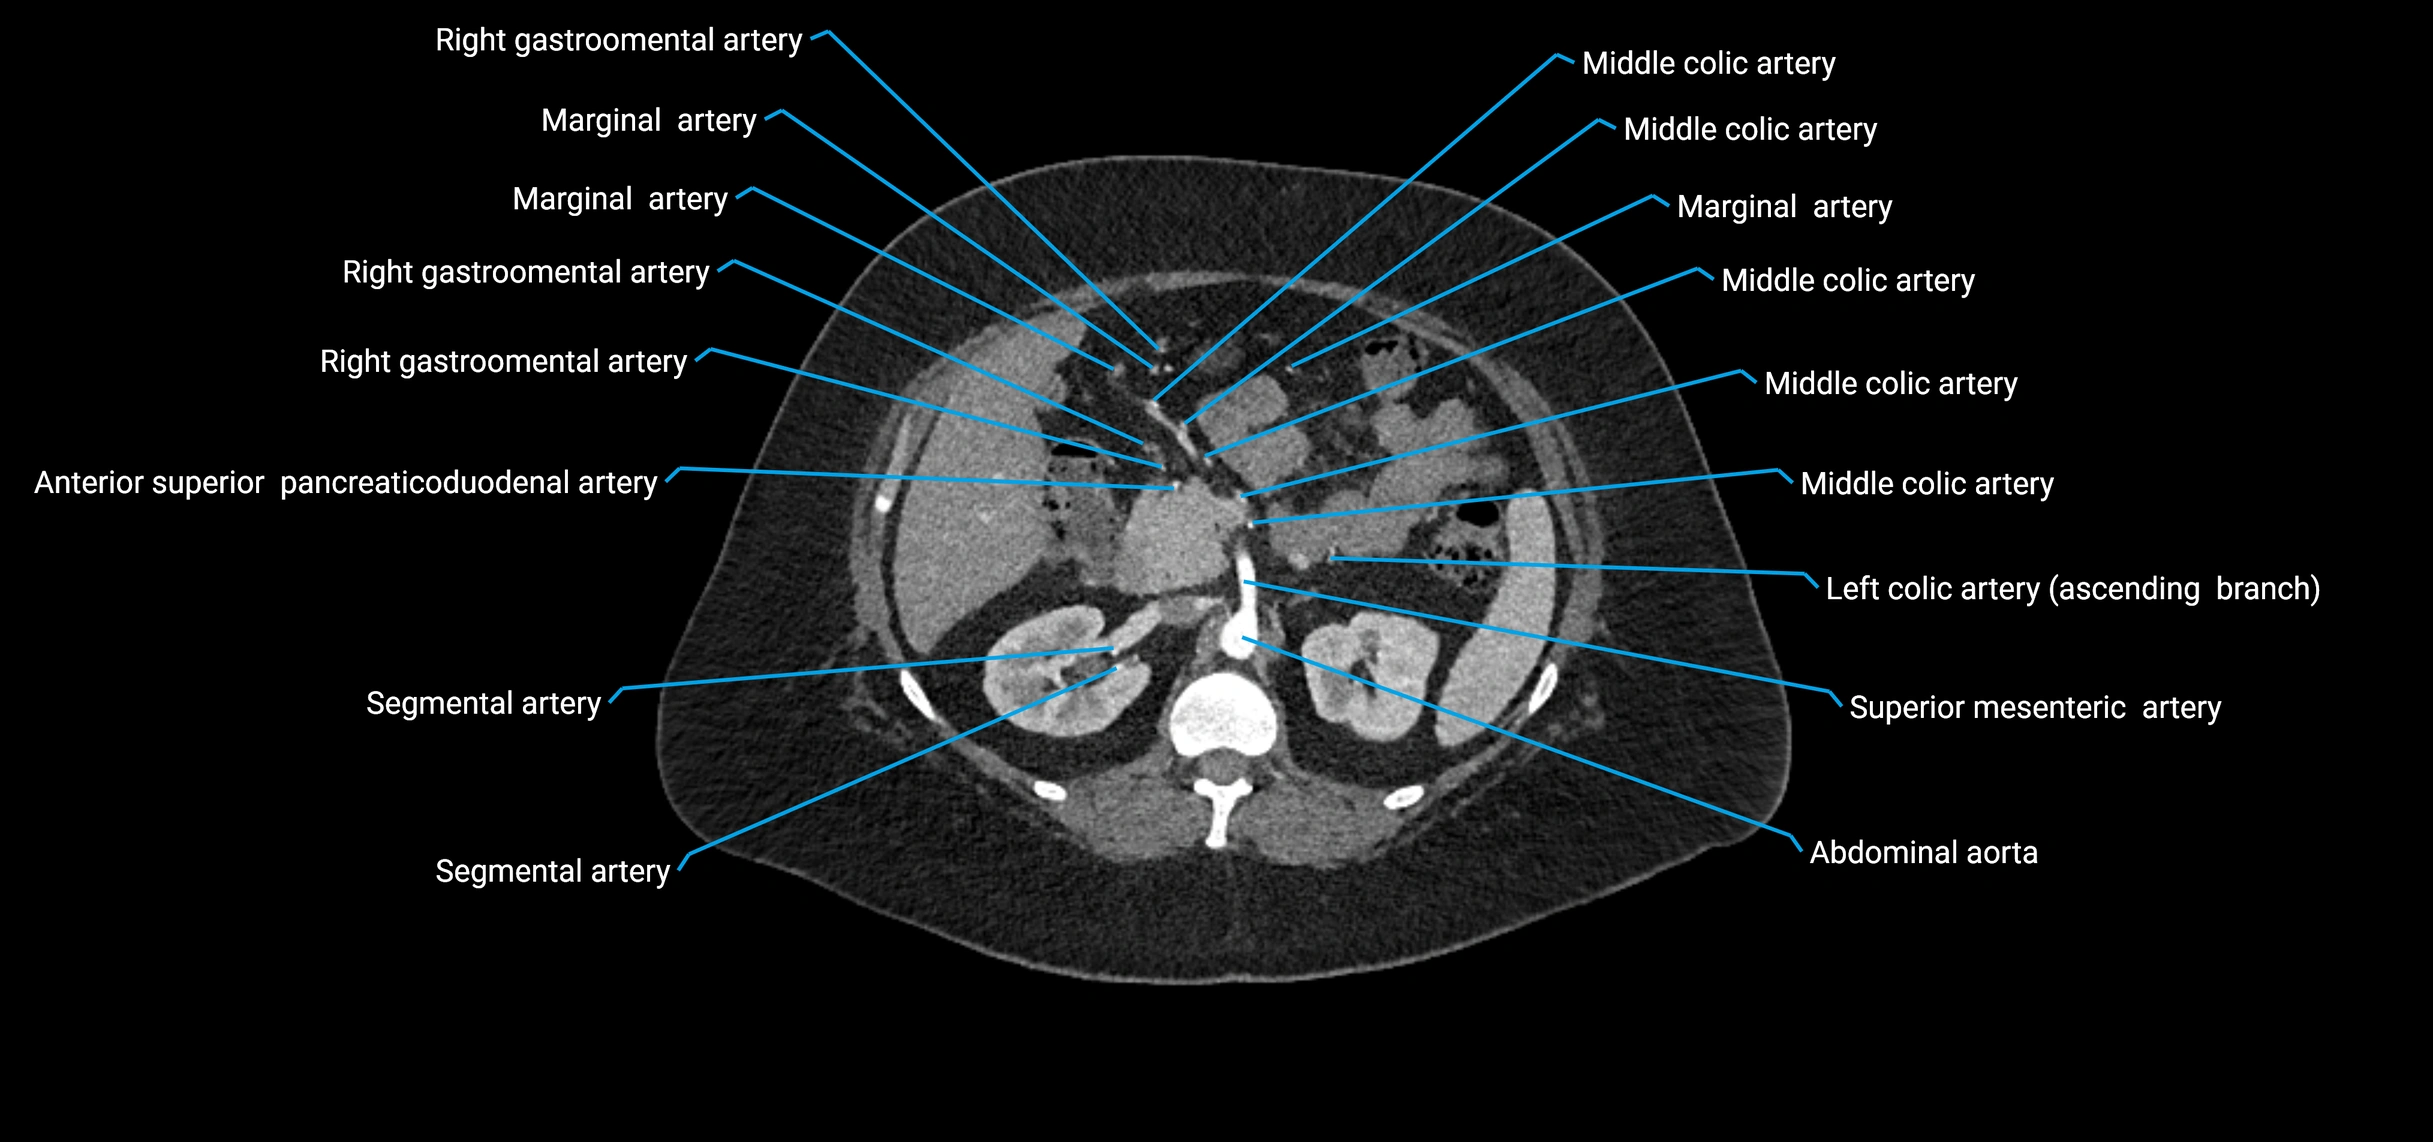

The abdominal aorta is the continuation of the thoracic aorta, beginning at the level of the aortic hiatus of the diaphragm (T12 vertebra) and terminating at the level of the L4 vertebra where it bifurcates into the right and left common iliac arteries. It lies slightly to the left of the midline and courses anterior to the vertebral bodies, surrounded by the retroperitoneal structures of the abdomen.

The abdominal aorta gives off numerous visceral and parietal branches, supplying the abdominal organs, pelvic structures, and lower limbs. It is the main conduit of oxygenated blood from the heart to the abdomen and lower body. The aorta is clinically significant as the common site of aneurysm, dissection, atherosclerosis, and traumatic injury.

Branches

• Unpaired visceral branches: celiac trunk, superior mesenteric artery (SMA), inferior mesenteric artery (IMA)

• Paired visceral branches: middle suprarenal arteries, renal arteries, gonadal arteries (testicular or ovarian)

• Parietal branches: inferior phrenic arteries, lumbar arteries, median sacral artery

CT Appearance

Contrast-enhanced CT (CTA):

• Gold standard for abdominal aortic imaging

• Provides excellent detail of lumen, wall, aneurysm, thrombus, and branch vessels

• Multiplanar and 3D reconstructions help in aneurysm measurement, stent graft planning, and dissection evaluation

• Detects acute rupture, traumatic injury, or occlusion with high sensitivity